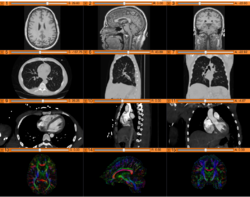

• The DICOM and Slicer tutorial provides an introduction to the DICOM standard and shows how to load and visualize DICOM datasets in 3D Slicer version 5.0.

• Author: Sonia Pujol, Ph.D.

• Modules: DICOM, Volumes

• Based on: 3D Slicer version 5.0/4.11

• The 3D Slicer DICOM Tutorial Data contains a torso-CT and a breast MRI.

• The 3D Visualization of DICOM images course guides through 3D data loading and visualization of DICOM images for Radiology Applications in Slicer4.

• Author: Sonia Pujol, Ph.D., Kitt Shaffer, M.D., Ph.D., Ron Kikinis, M.D.

• Audience: Radiologists and users of Slicer who need a more comprehensive overview over Slicer4 visualization capabilities.

• Modules: DICOM, Volumes, Volume Rendering, Models.

• Based on: 3D Slicer version 4.8

• Compatible with 3D Slicer version 4.10

• The 3DVisualizationDICOM_part1 and 3DVisualizationDICOM_part2 datasets contain a series of MR and CT scans, and 3D models of the brain, lung and liver.